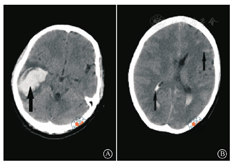

术后第1天产妇出现神志模糊,轻度躁动,皮肤苍白,伴间断性头痛,无恶心、呕吐。血压波动于134~155/78~99 mmHg,双侧瞳孔等大同圆,光反射灵敏,四肢活动轻度受限,肌力低,肌张力稍高,颈项强直,双侧病理征阴性,腹部伤口未见渗血,腹腔引流量少。急行脑部CT检查,提示右侧颞叶血肿急性期,蛛网膜下腔及侧脑室内积血(图1)。实验室检查提示丙氨酸转氨酶142 U/L,天门冬转氨酶97 U/L,乳酸脱氢酶816 U/L,血红蛋白48.1 g/L,血小板计数47×109 /L。